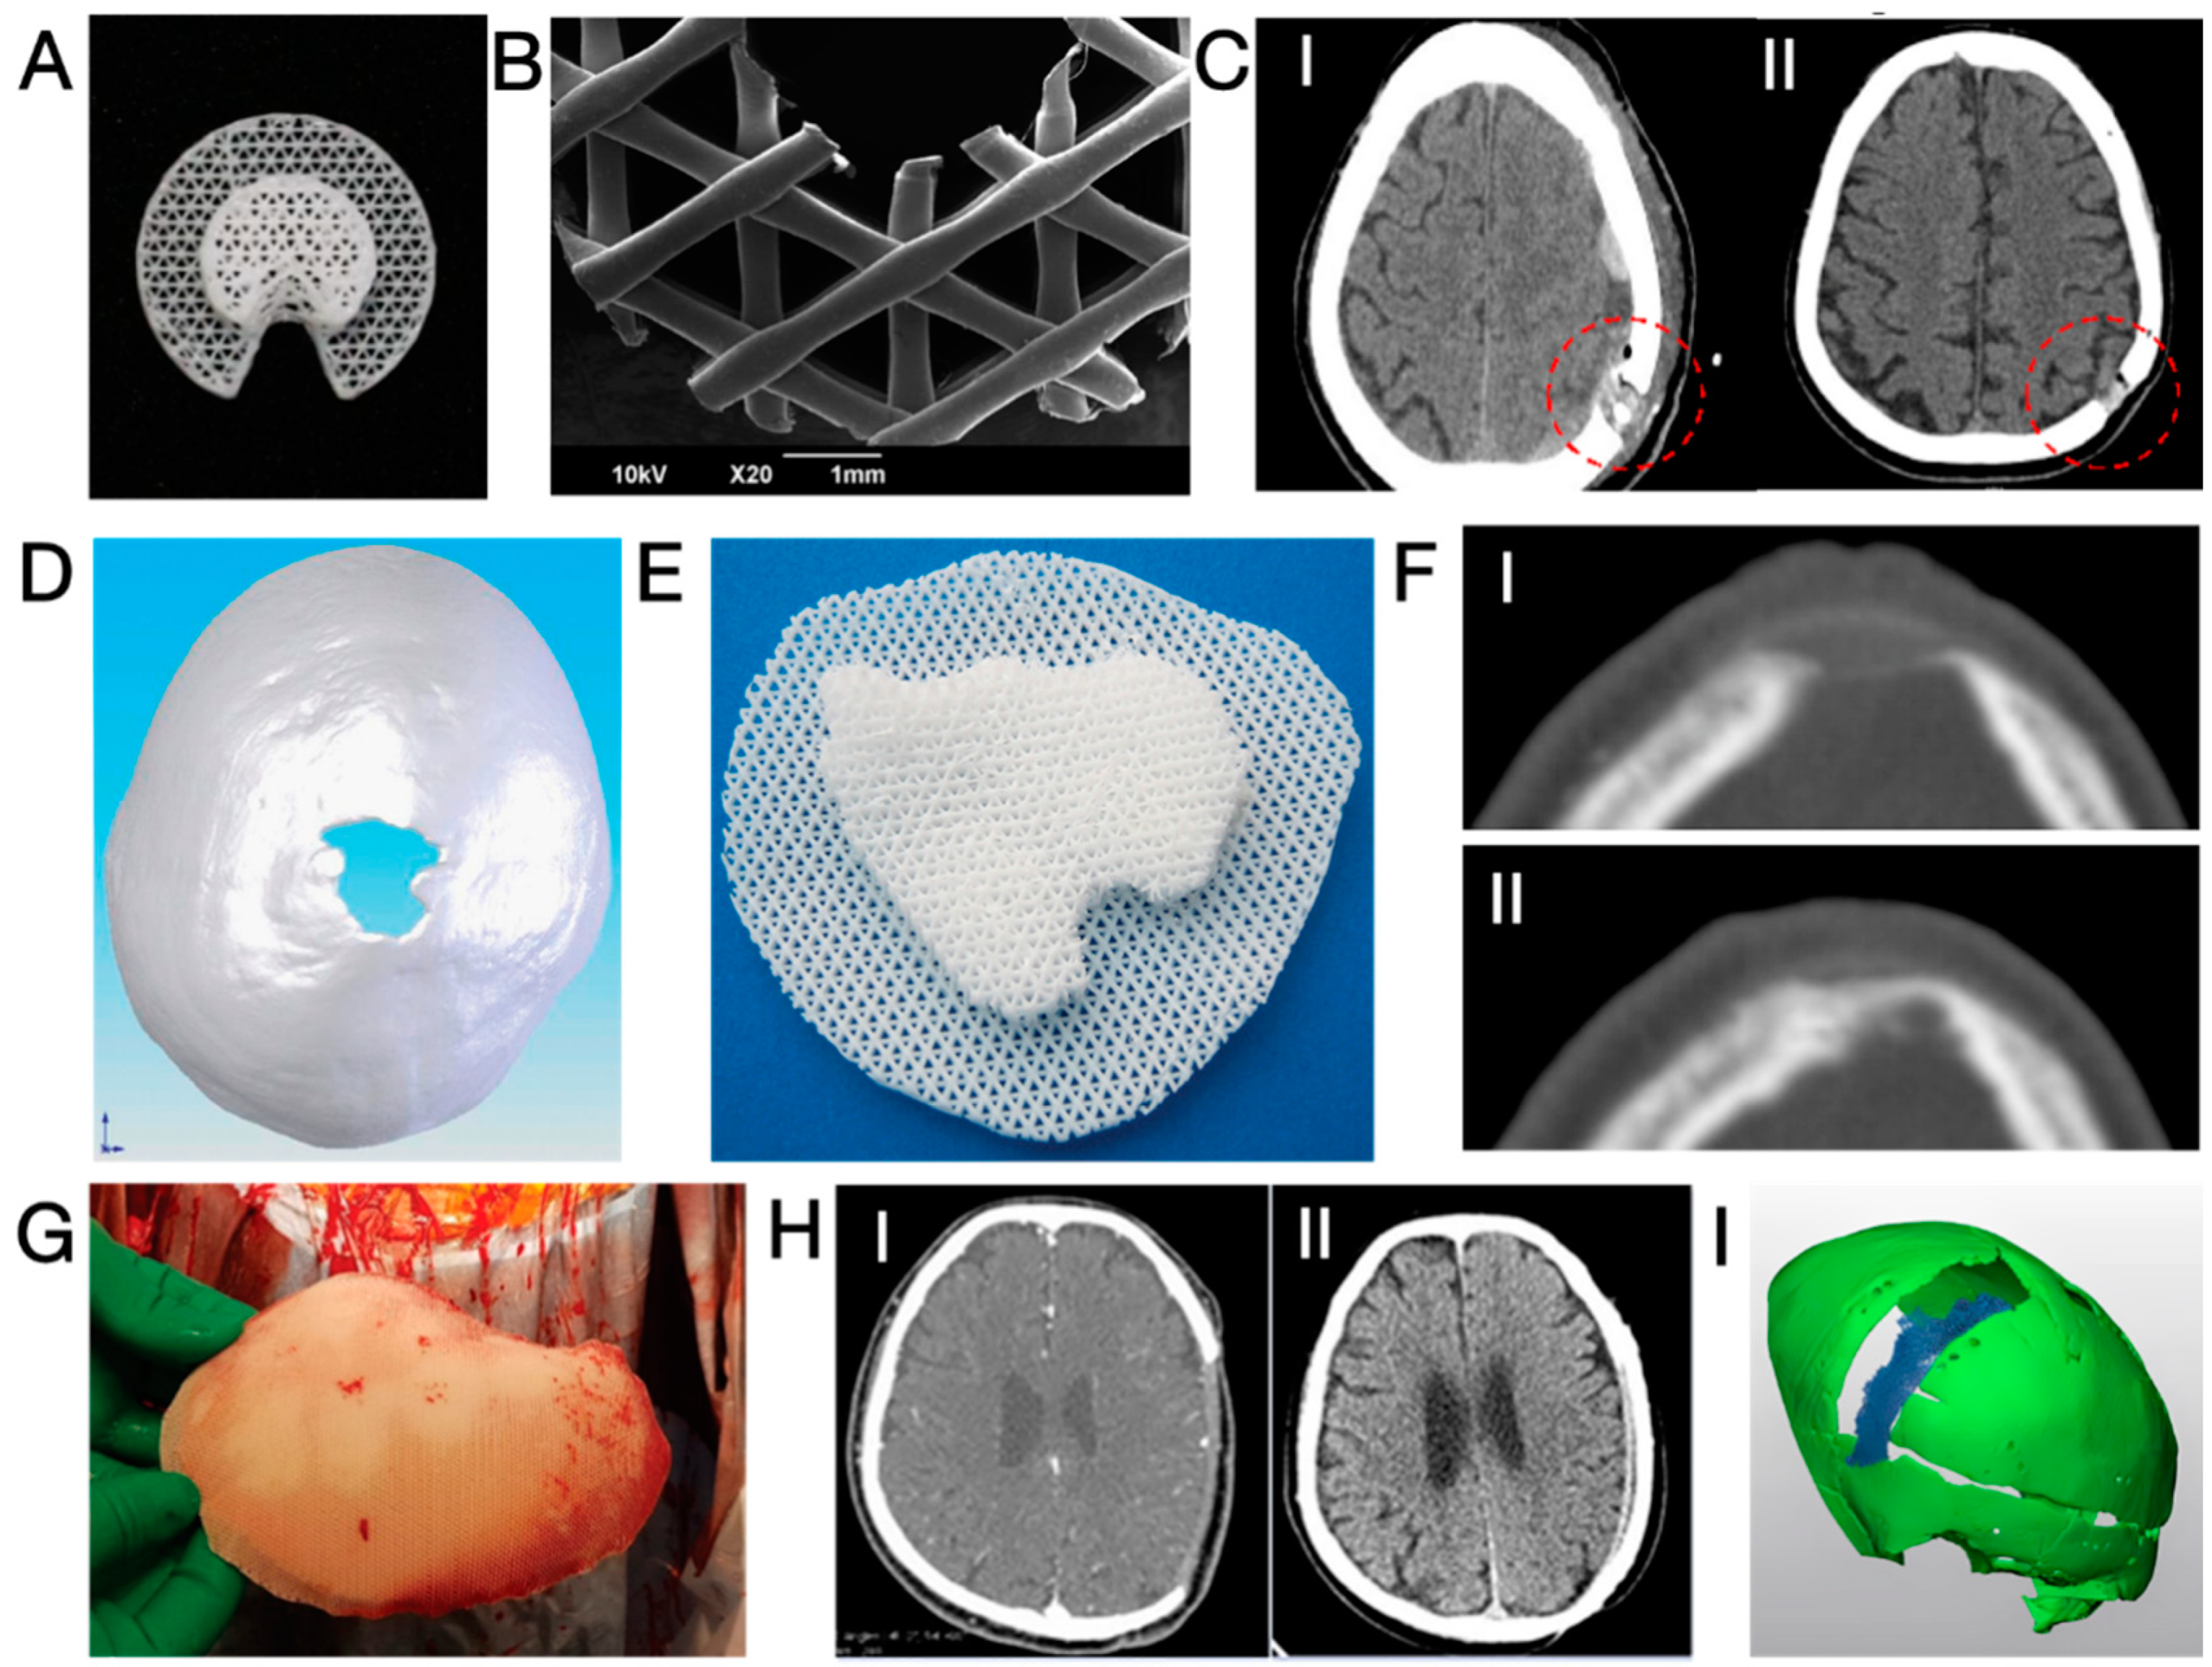

Figure 4.

(A,B) Photographs and microscopic images of Osteoplug® burr hole plug [104]; (C) CT images taken post-operatively (I) and at POM 15 (II), showing increased bone volume at the burr hole after implantation with a 3D-printed PCL plug. Red circles highlight the defected areas [103]; (D,E) a 3 × 3 cm2 cranial defect and the corresponding customised 3D-printed PCL cranioplasty implant [27]; (F) CT images of the defect shown in (D), taken post-operatively (I) and at POM 6 (II), showing bone regeneration [27]; (G) Photograph of a 3D-printed, customised PCL cranioplasty implant taken intraoperatively [106]; (H) CT images of a cranial defect (9.7 × 8.9 cm2) taken post-operatively (I) and at POM 20 (II), showing significant restoration of the cranium structure after reconstruction with a 3D-printed PCL implant [105]; (I) three-dimensional reconstruction of a band-shaped cranial defect at POM 12 after frontal-orbital advancement and cranioplasty using 3D-printed PCL mesh, showing a significant void surrounding the cranium (in green) and occupied by partly degraded PCL (in blue) [107]. Reprinted from Refs. [104,105,106]; Reprinted with permission from Ref. [103]. Copyright 2017, Future Medicine Ltd.; Ref. [27]. Copyright 2024, Georg Thieme Verlag KG; Ref. [107]. Copyright 2024, Wolters Kluwer Health, Inc., Philadelphia, PA, USA.

The first report on the neurosurgical application of 3D-printed PCL was published in 2006 [101]. In this study, five patients received 3D-printed PCL plugs (later commercialised as Osteoplug®, Osteopore, Singapore; see Figure 4A,B) to fill burr holes with a diameter of 14 mm. All plugs were coated with autologous blood and sealed with bone using fibrin glue. A 12-month follow-up revealed that all cases experienced uneventful recovery, achieving satisfying cosmesis. CT images indicated increasing bone formation since post-operative month (POM) 3 in the defective area of an 83-year-old patient. Similarly, another study reported 12 cases of uneventful burr hole reconstruction, observing simultaneous progressive bone regeneration [102]. Recent publications have noted that the use of PCL plugs resulted in effective bone regeneration after ~1 year (see Figure 4D) and significantly higher scores for both aesthetic outcomes and quality of life (QOL) without an increase in complication rates in comparison to patients with untreated burr holes who suffered from scalp depression [103,104].

The application of 3D-printed PCL in the reconstruction of larger cranial defects began in 2010 when Probst et al. repaired a 3 × 3 cm2 irregular cranial defect in an 11-year-old female; see Figure 4D–F [27]. To enhance bone-bonding bioactivity and stimulate bone growth, a PCL composite containing 20 wt.% of β-tricalcium phosphate (β-TCP) was utilised. CT images (Figure 4F) revealed signs of integration between the implant and the surrounding cranium six months after the surgery without any reported complications. Even larger implants (see Figure 4G) were successfully applied to induce cranium regeneration in later cases. In 2021, Hwang et al. reported two cases of cranioplasty using 3D-printed, patient-specific β-TCP/PCL in adults (21 and 25 years old), where the size of cranial defects exceeded 9 × 8 cm2 [105]. The implants underwent a 30 min immersion in bone marrow aspiration before being securely fixed into the defects. No complications were reported, and CT images (Figure 4H) indicated that the cranial defects were “completely filled” in both cases. The radiodensity within the defect after 8 months of implantation increased from 50 to 158 Hounsfield units (HU), demonstrating bone regeneration, although the radiodensity remained significantly lower than that of the native cranium (900–1000 HU). Koo et al. conducted a revision cranioplasty for a 73-year-old male using a 3D-printed PCL implant covered with a latissimus dorsi musculocutaneous flap [106]. After 1 year, a certain degree of bone regeneration and bone-implant integration was noticed.

Despite the previously reported uneventful healing, a recent study by Gonzales Matheus and Phua provides an alternative perspective [107]. The authors employed non-customised 3D-printed PCL meshes (without intraoperative immersion in blood or bone marrow aspirates) for cranial defect reconstruction during craniosynostosis correction surgeries in eight children. After 12 months, two patients exhibited noticeable voids without bone regeneration, while significant degradation of PCL was also noticed (see Figure 4I). In comparison to reconstruction using autologous particulate bone grafts, PCL implants resulted in inferior bone regeneration after 9 months post-operatively. The authors suggested that the non-bioactive PCL implant occupied the defective area and hindered intrinsic tissue regeneration.